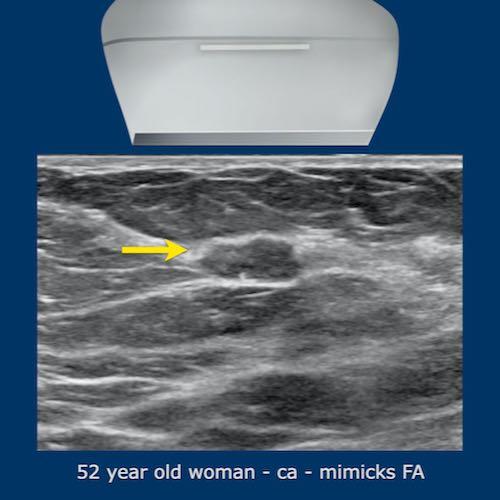

Đôi khi ung thư vú có thể có hình ảnh tương tự u xơ tuyến vú và ngược lại, u xơ tuyến vú cũng có thể có hình ảnh siêu âm giống ung thư.

Bảng dưới đây liệt kê các điểm khác biệt về hình ảnh siêu âm giữa hai loại tổn thương này.

Tuổi của bệnh nhân cũng là một yếu tố quan trọng cần xem xét, vì u xơ tuyến vú thường gặp ở phụ nữ trẻ, đặc biệt trong độ tuổi 15-25 và hiếm gặp ở phụ nữ trên 50 tuổi, trong khi ung thư vú được chẩn đoán phổ biến nhất ở phụ nữ trên 50 tuổi và ít gặp hơn ở phụ nữ trẻ.

Trong một số trường hợp, không thể phân biệt được hai loại tổn thương này chỉ dựa vào hình ảnh siêu âm đơn thuần và cần phải sinh thiết để có chẩn đoán xác định.

Hình ảnh cho thấy một tổn thương mà thoạt nhìn có vẻ giống u xơ tuyến vú.

Tuy nhiên, có hai điểm không phù hợp.

Thứ nhất, tuổi của bệnh nhân là 49 tuổi và thứ hai, bờ phía sau của tổn thương có một số chỗ không đều.

Sinh thiết đã được thực hiện và khối này được xác định là ung thư.